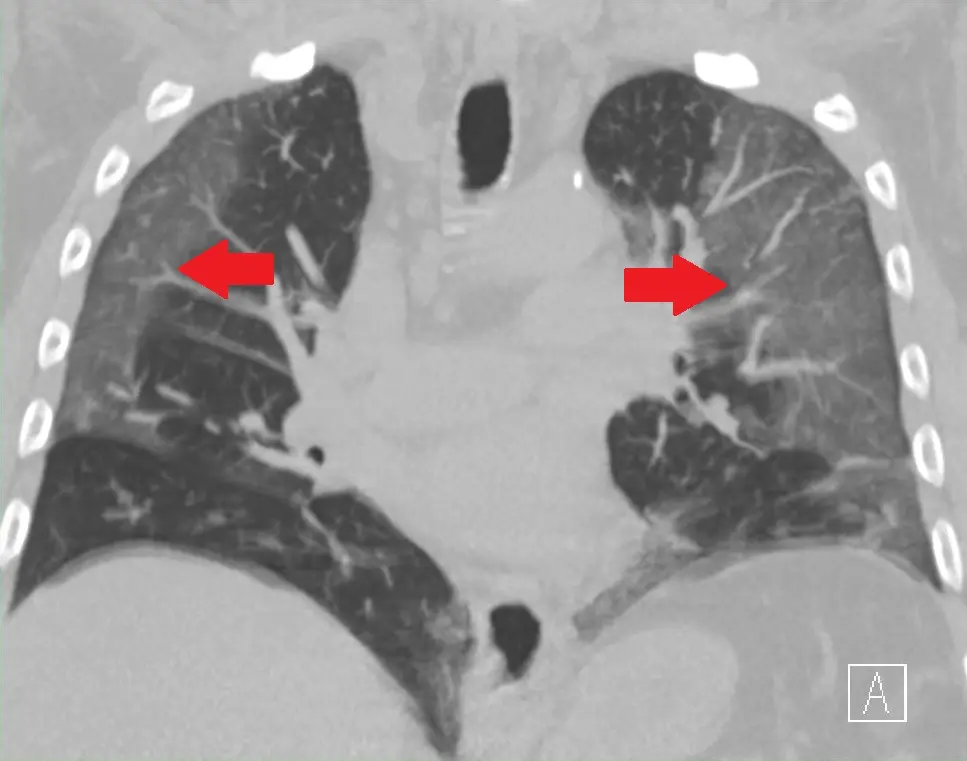

Stage 3: Hypoxia, ground glass infiltrates, and progression to ARDS In about 20% of the patients, the disease progresses to stage 3 and they develop pulmonary (lung) infiltrates. And some of them will develop severe disease. The virus starts to infect the alveolar (microscopic air sacs) cells and replicate inside killing the cells in the process. This leads to death of alveolar cells and secretion of fluids and infiltration of immune cells into the alveoli. This is the reason for developing groud glass opacities in the radiographs (CT and X-Rays)(Fluids appear opaque (white) on an x-ray compared to air).

![]() |

|---|

| Ground Glass Opacities in High Resolution Computed Tomography (HRCT) image of Chest. |